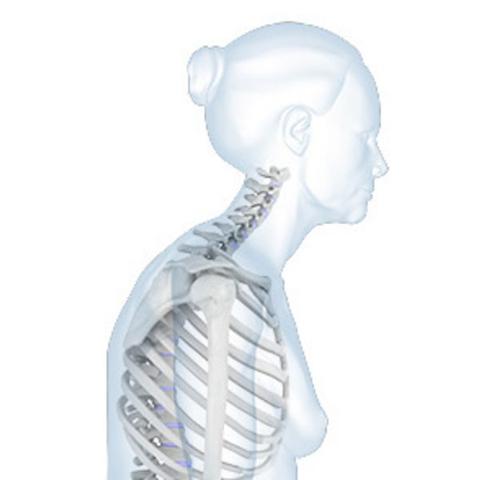

Besonders gefährlich sind Brüche in der Wirbelsäule, da sie zu Schmerzen, einer gekrümmten Haltung und einer Verringerung der Körpergröße führen können. Zudem können Wirbelkörperfrakturen zu Einschränkungen der Beweglichkeit und einer Verschlechterung der Lebensqualität führen.

Das Risiko für Osteoporose-bedingte Komplikationen steigt mit zunehmendem Alter und je weiter die Krankheit fortschreitet. Besonders kritisch wird es, wenn bereits mehrere Knochenbrüche aufgetreten sind oder wenn die Wirbelsäule betroffen ist. Ein Einsturz von Wirbelkörpern kann zu starken Schmerzen und einer Einschränkung der Beweglichkeit führen.

– Starke Rückenschmerzen oder ein abgerundeter Rücken (Kyphose), verursacht durch eingeklemmte oder gebrochene Wirbel.

– Schrumpfung der Körpergröße aufgrund des Verlusts an Knochenmasse.